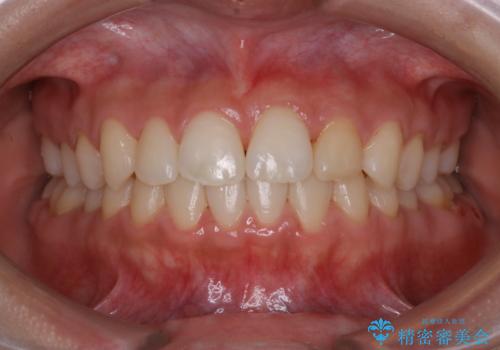

1カ月前に他院でクリーニングを受けたが舌触りが気になる PMTCでツルツルに